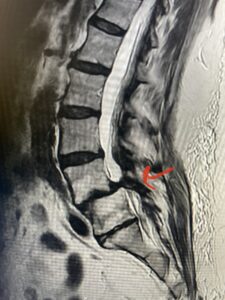

Fig 4: Sagittal T2-weighted lumbar MRI demonstrating L3-4 grade 1 spondylolisthesis with severe stenosis (blue arrow)

Another patient is a 62 year-old female with progressive low back pain and right leg pain and numbness that radiates to the top of her foot. She tried physical therapy and epidural injections. MRI demonstrated severe L3-4 stenosis and a grade 1 spondylolisthesis (Fig 4). There was L5-S1 and L4-5 disc collapse with modic end-plate changes. Biomechanically because of the significant degeneration of these disc spaces which stiffened the L4-S1 segment more stress was placed on the L3-4 segment, resulting in significant premature degeneration and compensatory stenosis and segmental instability. The MRI also showed pathologically, because of the slip, the L3 inferior processes were more anteriorly oriented and hence contributing to the majority of the lumbar canal compromise. Note the more sagittally-oriented facets in this case compared to the prior case (Fig 5). The patient underwent a decompressive laminectomy with attention of removing the inferior processes of L3 to fully decompress the canal. We also performed an L3-4 fusion with instrumentation (Fig 6). The patient had an uneventful postoperative course with improvement of leg pain. Of note with relief of the disabling leg pain patients are generally very happy. Patients can often manage their low back pain; it is the leg pain that they just can’t tolerate.